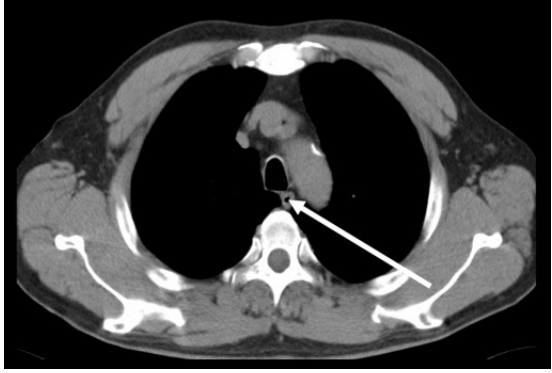

35.下圖中箭號所指示的位置為下列何者? (A)trachea (B)brachiocephalic vein (C)subclavian artery (D)esophagus